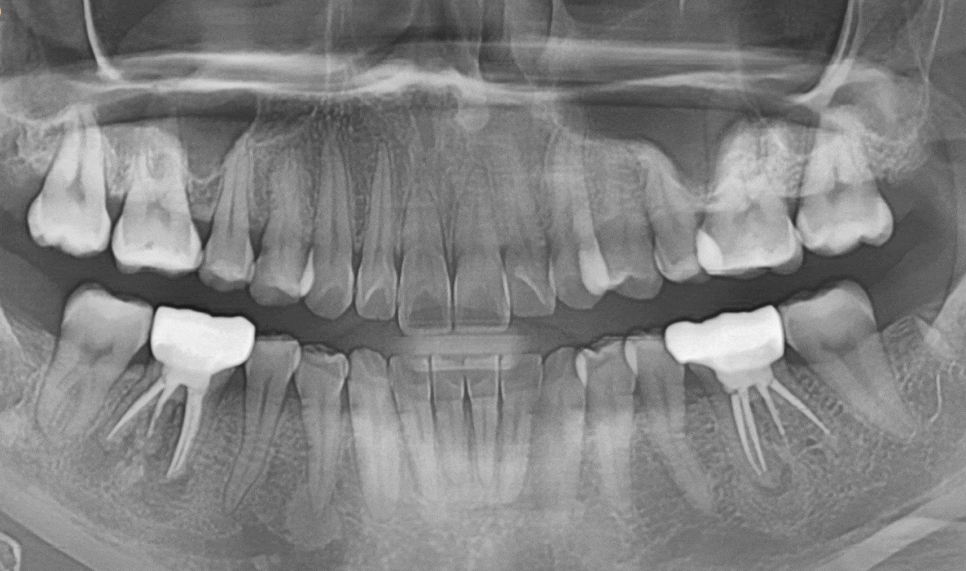

이미 신경치료는 다 되어 있고

사진상에도 치아 뿌리에

염증이 심하게 생긴 상태였어요.

250602 뿌리 끝 염증으로 뼈가 녹은 상태

CT를 찍어보니 뼈 소실이 생각보다 많이 진행되어 있었습니다.

당일 발치 후 바로 뼈이식과 함께 임플란트를 심었습니다.

이렇게 즉시 식립하면 뼈 손실을 최소화할 수 있거든요.

250715

정확한 각도와 위치에 심어졌습니다.

2달 후 다시 내원하셨을 때

뼈에 임플란트가 잘 붙었는지 확인해 봤어요.

전 : 250602 / 후 : 250725